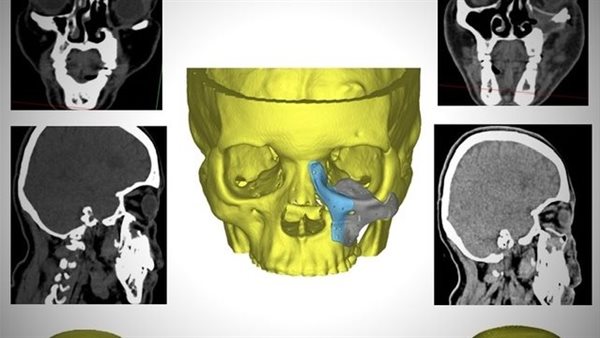

أطباء مستشفى الكرنك الدولي بالأقصر ينجحون في إعادة بناء عظام وجه سيدة بعد إصابتها بالفطر الأسود

استطاع أطباء جراحة الوجه والفكين وأورام الرقبة بمستشفى الكرنك الدولي بالأقصر من إعادة بناء عظام الوجه لسيدة أربعينية بعد تآكل عدة أجزاء منها نتيجة الإصابة بالفطر الأسود جراء جائحة كورونا.

وقال بيان لهيئة الرعاية الصحية، إن السيدة جاءت للمستشفى وهي تعاني من تسوس وتآكل بعظام الوجه وحجاج العين مما استدعى مثول السيدة للعديد من الجراحات التي أدت في النهاية لتشوه عظام الوجه على مدار 4 سنوات من المعاناة، وفقدت السيدة الأمل في مواجهة تحديات كبيرة نتيجة تشوه الوجه ورفض الكثير التدخل الجراحي.

وأضاف البيان، أن قسم جراحة الوجه والفكين بمستشفى الكرنك الدولي اتخذ القرار الطبي بعد استقرار حالة المريضة والمتابعة المستمرة للتأكد من إمكانية التدخل باستخدام التقنيات الحديثة لإعادة البسمة والأمل والثقة للسيدة في علاج التشوه الشديد بالوجه.

جراحة استغرقت 6 ساعات

وأشار البيان إلى استخدم القسم تصميم معقد مصنوع من مادة الـpeek والمستخدمة حديثًا في استيعاض عظام الوجه وذلك من خلال جراحة دقيقة استغرقت حوالي 6 ساعات.